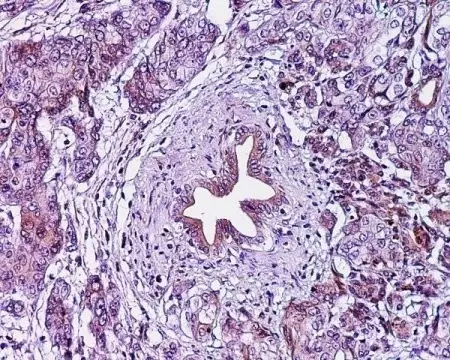

在所有类型的胰腺癌中,胰腺导管腺癌(PDAC)是最为常见的,占85-90%[1],而患者总体的5年生存率仅有7%[2],这一数字在近20年来都没有改善[3]!手术切除加上术后化疗是目前临床上最常用的治疗方法,可以明显延长生存期,这类患者5年生存率能够达到27.1%[4],但手术切除通常只能在癌症早期(I、II期)进行,一旦出现了远端转移,那么手术切除可能就失去了意义。

PDAC患者组织切片染色